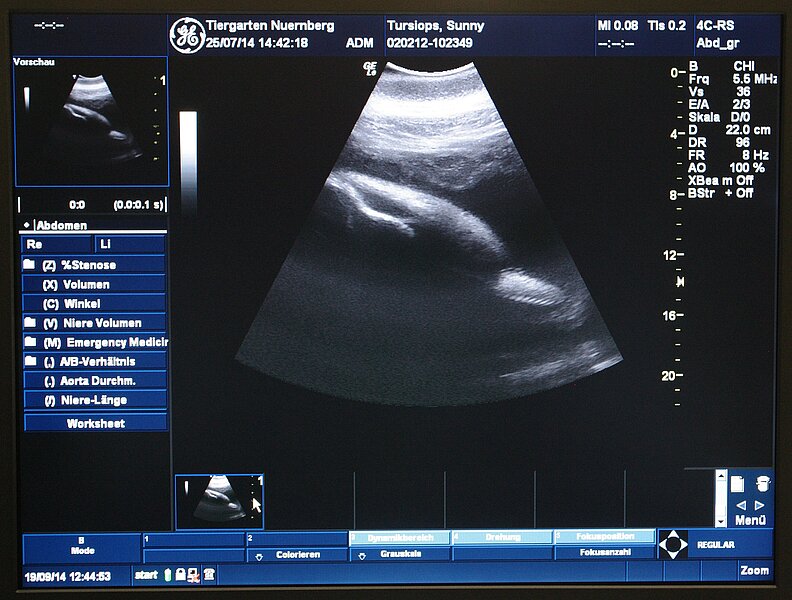

Die Geburt eines Delphinkalbs im Tiergarten der Stadt Nürnberg rückt näher: Nach einer langen zeitlichen Pause steht die Niederkunft bei dem weiblichen Tier Sunny bevor. Die Geburt ist in den nächsten Wochen zu erwarten. Die letzten Ultraschall-Untersuchungen zeigen ein normal entwickeltes Kalb, das in Bezug auf Größe und Herzschlag in einem guten Zustand ist.

Die Vorbereitungen auf die Geburt laufen bereits seit längerer Zeit. Dafür wurden Erfahrungen von Delphinarien aus vielen Ländern gesammelt sowie Vorgehensweisen besprochen. Es wurde ein detailliertes Protokoll erstellt, sodass die Eingriffe im Falle einer Unregelmäßigkeit bereits vorab festgelegt werden. Diese Vorbereitungen verfolgen das Ziel, möglichst viele mögliche Vorkommnisse im Rahmen und im Nachgang der Geburtzu bedenken und für die Fälle vorbereitet zu sein, bei denen eine

menschliche Intervention notwendig und sinnvoll sein kann. Fälle, in denen der Tiergarten eine Intervention für sinnvoll hält, sind unter anderem unregelmäßiges Trinkverhalten und/oder fehlende Milchwolken beim Saugvorgang, Anzeichen für Schwäche beim Kalb sowie oberflächliche Verletzungen, die eine Infektion nach sich ziehen könnten.

Die erste Voraussetzung für eine tiermedizinische Intervention ist die Möglichkeit, das Kalb untersuchen zu können. Dafür wurde im Zuge des Neubaus der Lagune ein Hebeboden in das für die Geburt vorgesehene Becken eingebaut. Mit Hilfe dieses Hebebodens können Mutter und Kalb schonend in niedriges Wasser gehoben werden, sodass Routine- Untersuchungen des Kalbs im Wasser stattfinden können. Diese Vorgänge werden seit Monaten wiederholt mit Sunny geübt, sodass sie daran gewöhnt ist.

Bei der Neukonzeption der Delphinhaltung in Nürnberg wurden zwei Faktoren maßgeblich weiter entwickelt. Durch den neuen Hebeboden ist es nun möglich, das Kalb im Wasser zu untersuchen und gegebenenfalls bei Bedarf zu behandeln. Damit kann nun mit Delphinkälbern wie mit allen anderen Jungtieren im Tiergarten verfahren werden.